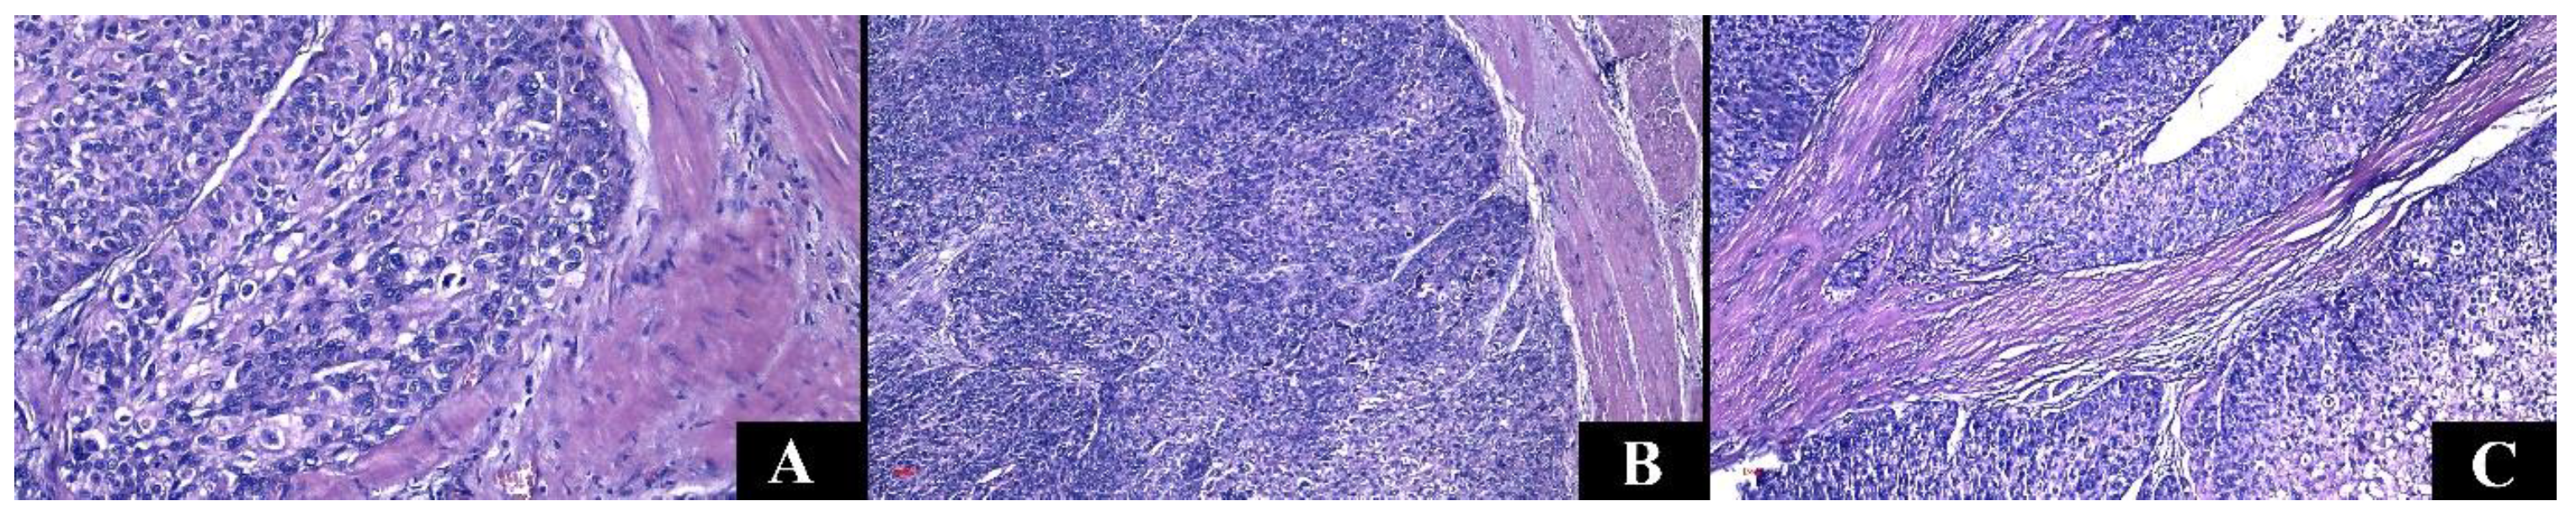

| Renal Cell Carcinomas | Upper Tract Urothelial Carcinomas | p-Value | |

|---|---|---|---|

| Tumor necrosis | 56.69% | 61.29% | 0.694 |

| Hemorrhagic infiltrate | 72.61% | 38.71% | 0.001 |

| Intratumoral inflammatory infiltrate | |||

| Acute | 2.55% | 0% | 0.41 |

| Mixed | 8.92% | 16.13% | |

| Chronic | 88.53% | 83.87% | |

| Angiolymphatic invasion | 22.92% | 48.39% | 0.007 |

| Perineural invasion | 7.64% | 29.03% | 0.002 |

| Histological grade | ISUP 2—41.40% | ||

| Low grade (1 and 2) | 55.41% | 38.71% | - |

| High grade (3 and 4) | 44.59% | 61.29% | 0.115 |

| pT | 3a—31.21% | 3—64.52% | - |

| Metastasis (n) | 2—lung | 2—bone | - |

| Complete resection | 98.73% | 87.10% | 0.007 |

| Adjacent renal parenchyma | 0.001 | ||

| Chronic pyelonephritis | 35.67% | 70.97% | |

| Normal | 31.85% | 3.23% | |

| Interstitial nephritis | 25.48% | 19.35% | |

| Hydronephrosis | 1.27% | 6.45% |

| Tumor Type | Variants | Gross Aspect | Origin | Histologic Features |

|---|---|---|---|---|

| Clear cell renal cell carcinoma |

| Pseudoencapsulated Golden yellow Necrosis Hemorrhage | Tubular epithelium Proximal nephron | Nests and sheets of cells with clear cytoplasm. |

| Papillary renal cell carcinoma |

| Often pseudoencapsulated Solid or cystic Whitish Necrosis Hemorrhage | Tubular epithelium Distal nephron | Thin or thick papillae lined by uni- or pseudostratified cuboidal epithelium, foamy macrophages, and psammomatous bodies. |

| Chromophobe renal cell carcinoma |

| Well defined Gray to tan-brown Central scar | Intercalated cells of the distal tubules Distal nephron | Cells with prominent membrane and pale/eosinophilic cytoplasm. |

| Carcinoma of collecting ducts | Partially cystic Grayish-white | Collector tubes | Tubulopapillary architecture, hobnail cells, mucinous material, desmoplastic stroma. | |

| Flat or exophytic lesion | Urothelium | Varying degrees of cytoarchitectural atypia (fusion of papillae, disorganized tumor cells); cells with moderate or increased pleomorphism and mitotic activity. |

| Invasive urothelial carcinoma |

| Sessile, polypoid, nodular, or ulcerative lesion | Urothelium | Urothelial cells with high-grade atypia can associate divergent differentiation. Various architectures: papillary, micropapillary, nested, or tubular. |